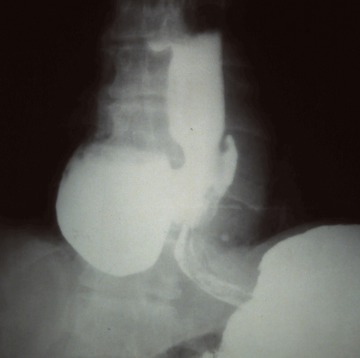

위조영술 검사는 바륨이라는 하얀 액체를 마시고 그 액체가 식도를 타고 내려가면서 위에 쌓였을 때 몸을 이리저리 뒤집어가면서 그 흑백화면을 보면서 읽어내는 검사방법입니다.

바륨현탁액, 요오드제제를 이용해 위의 이상 유무를 검사합니다. 이 용액은 X선 투과가 잘 안되는 물질로 이 용액을 마시고 X선이 발생되는 기계 위에서 몸을 이리저리 돌려가면서 검사를 받습니다. 기계가 알아서 돌아가는 것이 아니라 사람이 직접 그 기계 위해서 몸을 움직여 줘야 합니다.

X선이 발생하는 기계 위에 있으므로 그 방사선이 몸을 투과하므로 미량의 방사선 피폭이 있다는 것은 인지해야 합니다. 위조영술 검사방법은 위를 풍선처럼 팽창시켜 위벽에 조영제 코팅해 위벽 병변 유무를 검사하는 방법과 위가 팽창하지 않은 상태에서 위를 조영제로 채워 검사하는 두가지 방법이 있으며 일반적으로 두가지 다 시행해야 위벽과 안을 다 검사 할 수 있습니다.